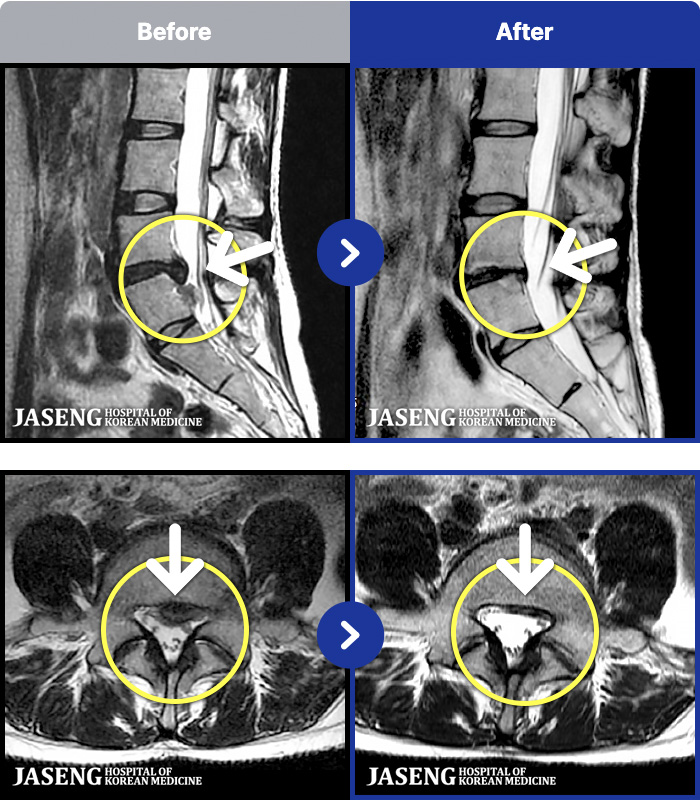

- MRI ġ

MRI ġ

181 MRI ũ ʸ Ȯϼ.

㸮 ϻ .